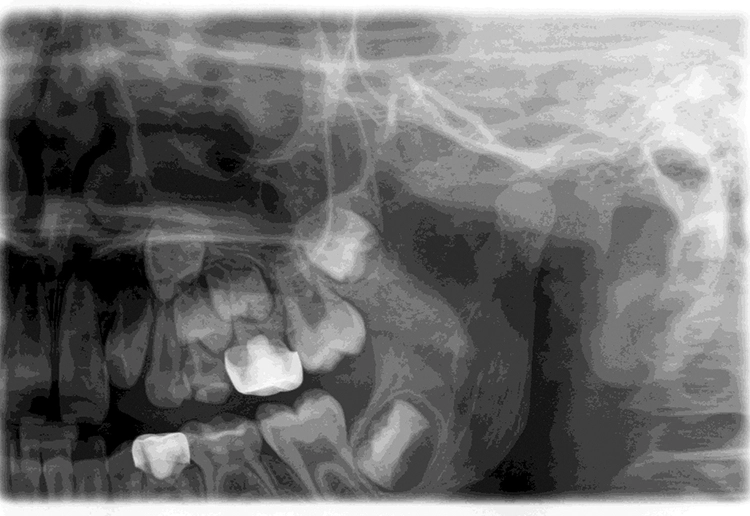

Bei einem Kontrolltermin eines 8-jährigen Jungen imponierte eine insuffiziente Füllung im linken Oberkiefer (Abb. 1). Die Anfertigung eines halbseitigen Orthopantomogramms (OPG) zeigte eine koronale Aufhellung an Zahn 64 distal (Abb. 2). Aufgrund der vollständigen mesialen Wurzel entschied man sich für den Erhalt des Zahnes 64 und eine Restauration mit einem plastischen Füllungsmaterial.